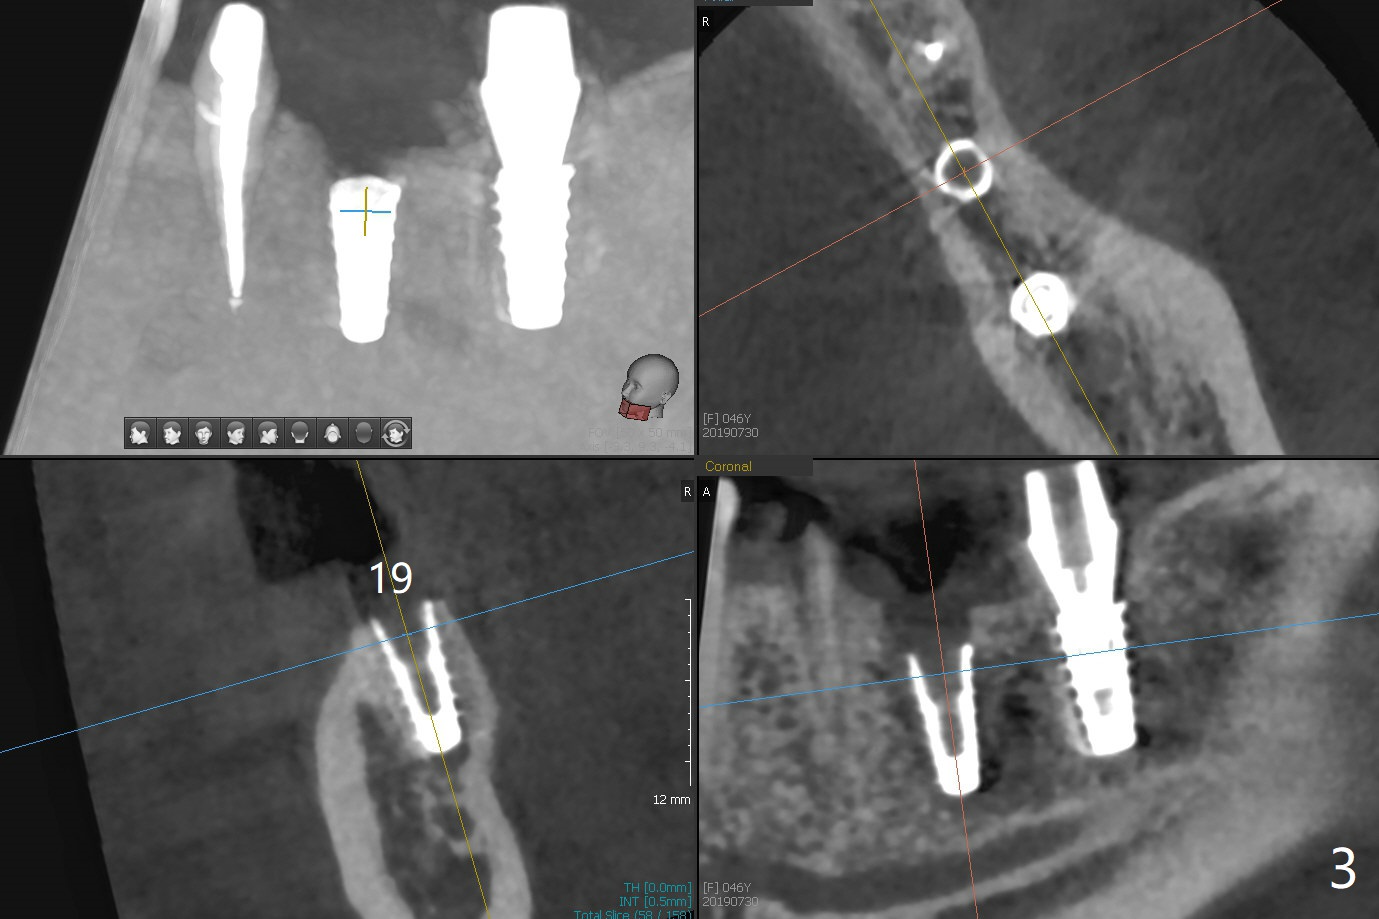

The female woman is afraid of pain. After placement of 4x9 mm FC implant at #19, infiltration anesthesia is not enough for osteotomy at #18. Block anesthesia is added. When a 5x9 mm FC implant is placed in the osteotomy (designed for 5x8.5 mm IS one), it is close to the Inferior Alveolar Canal (Fig.1 red dashed line; Fig.2 (*: bone graft with PRF)). The third contributing factor is the pressure upon the distal end of the distal end guide while osteotomy. A few hours later, the patient reports no paresthesia. The implant placement level and trajectory are normal at #18 and 19 (Fig.3-5). To check pair abutment seating with 30 Ncm torque, PA is taken after removal of healing abutments 4 months postop (Fig.6-8). First the cuff of the abutment is short, subgingival distal of #18 (Fig.6 * (gingiva)). When an abutment with longer cuff is placed, it appears to be close to the distal crestal bone (Fig.7 *). Finally a smaller abutment seams to be appropriate (Fig.8). Retrospectively the larger abutment (6.5x4(4) mm) is incompletely seated initially (Fig.1 with gap).